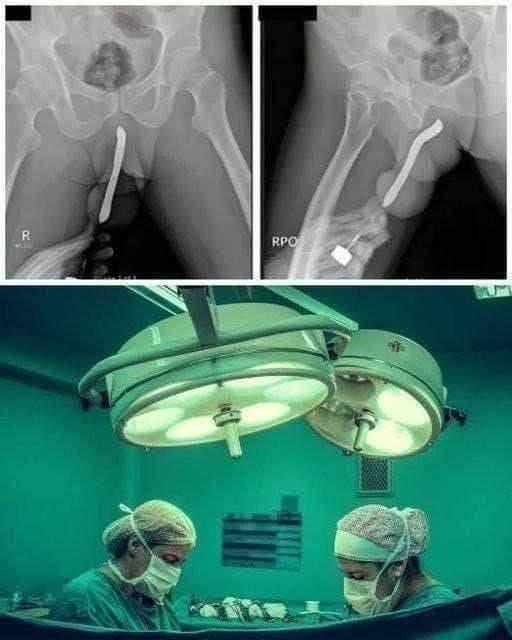

You sit at your kitchen table on an ordinary afternoon, reading about a disturbing case that has doctors issuing urgent warnings to parents. A young girl was rushed to the hospital after inserting a pen into her body in a dangerous way. The object caused severe internal lacerations, significant tissue damage, bleeding, and a high risk of infection that required emergency surgery.

Medical staff were able to stabilize her, but experts emphasize how easily this could have resulted in permanent damage to reproductive organs, life-threatening infections like sepsis, or even death. The incident highlights a troubling trend among some teens experimenting with foreign objects in unsafe ways, often driven by curiosity, peer pressure, or lack of proper education.